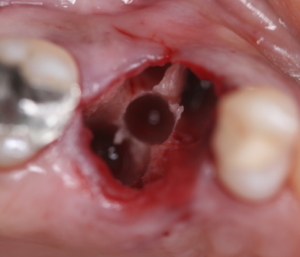

Vista oclusal do elemento16 pós-instrumentação.